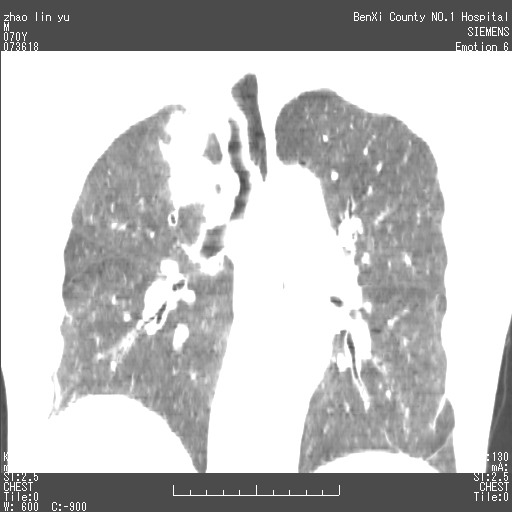

以下是引用王靖旗在2007-7-10 17:12:00的发言:[br] 男、70、咳嗽两个月,半年前换瓣手术,胸片未见异常,于昨天行x片发现右肺上野大片影,行ct扫描,这里是减薄图像,余肺正常。明天晚上会有增强扫描片,到时我会上传。[br][br] 冠状位请大家细看,应该是有意义的,[br][br] 请大家先看平扫发表意见。[br][br]

[br]冠状面[br]

以下是引用zhangzhongshou在2007-7-10 21:43:00的发言:[br]右肺上叶周围型肺癌,以孤立型细支气管肺泡癌可能性大。